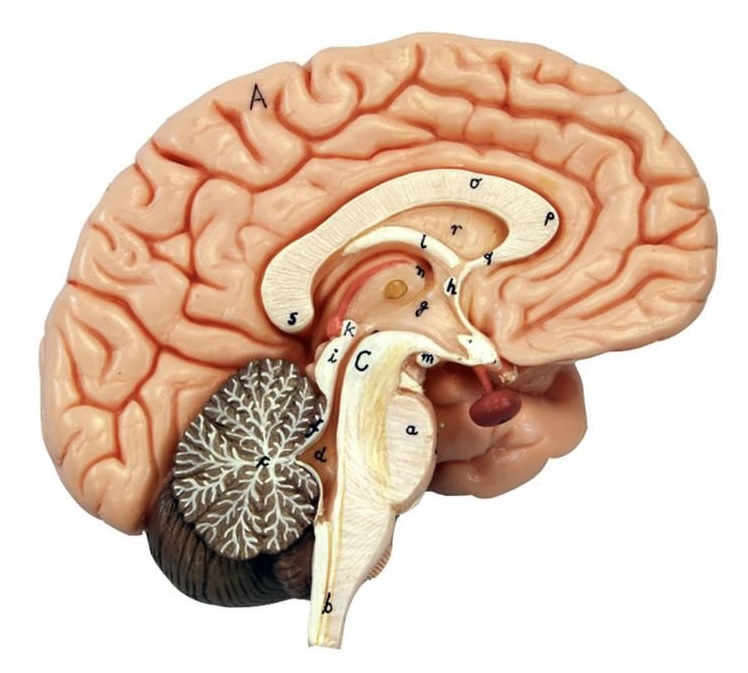

What is C?

3rd ventricle

What is B?

cerebral aqueduct

What is A?

4th ventricle

What is below A at the very end?

central canal (spinal cord)

What is C?

midbrain

tectum (corpora quadrigemina): superior colliculus

tectum (corpora quadrigemina): inferior colliculus

What is a?

pons

medulla oblongata

intermediate mass of thalamus

hypothalamus

What is the pink bulb?

pineal gland

corpus callosum

fornix

What is A?

cerebral cortex

cerebral tracts

cerebral hemispheres

longitudinal fissure

What are these ridges?

gyri

What are these shallow grooves?

sulci

Divides parietal from frontal lobe

central sulcus

precentral gyrus

postcentral gyrus